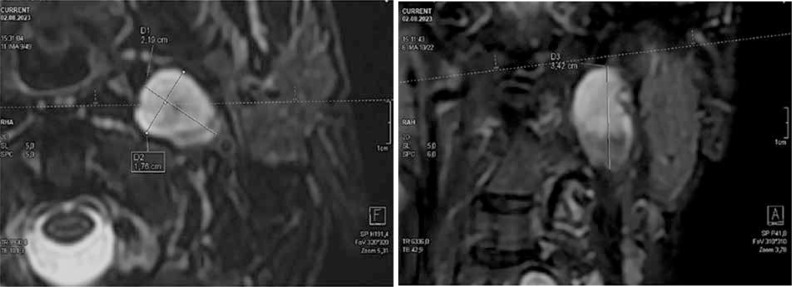

1型神经纤维瘤病(NF1)是一种遗传决定的疾病,具有复杂的临床症状,包括许多系统和器官的疾病,易导致各种癌症的发展。大约10-30%的NF1患者发展为丛状神经纤维瘤(PN),这是一种沿神经生长的非恶性肿瘤,易于浸润神经和神经丛,并可能生长到内脏器官、椎管、中耳、骨骼变形和身体的各个部位。核磁共振成像(MRI)作为一种基线筛查工具,在PN过程中的个体管理中起着关键作用,用于监测(已知PN个体),评估治疗反应,以及术前评估手术计划。本文提出的实用建议旨在规范NF1过程中PN的MRI检查方案,以便在波兰的临床项目中进行治疗。该方案包括体积MRI检查,成像时间表,目标变化的确定,测量病变体积的技术,以及怀疑的恶性转化,旨在成为这些患者每次检查中必须包含的最小MRI序列和视图集。

Neurofibromatosis type 1 (NF1) is a genetically determined disorder with a complex clinical picture, including disorders of many systems and organs, that predisposes to the development of various cancers. Approximately 10-30% of patients with NF1 develop plexiform neurofibromas (PN), non-malignant tumours growing along the nerves, tending to infiltrate nerves and nerve plexuses, and may grow into internal organs, the spinal canal, and middle ear, deforming bones and various regions of the body. Magnetic resonance imaging (MRI) plays a key role in the management of individuals during the course of PN, as a screening tool at baseline, for surveillance (in individuals with known PN), to evaluate treatment response, and for preoperative assessment for surgical planning. The practical recommendations presented in this article aim to standardise the protocol for MRI examination of PN in the course of NF1 for the purpose of treatment in a clinical program in Poland. The protocol, covering volumetric MRI examination, imaging schedule, determination of the target change, the technique for measuring the volume of lesions, and suspected malignant transformation, is intended to be the minimum set of MRI sequences and views that must be included in every examination of these patients.